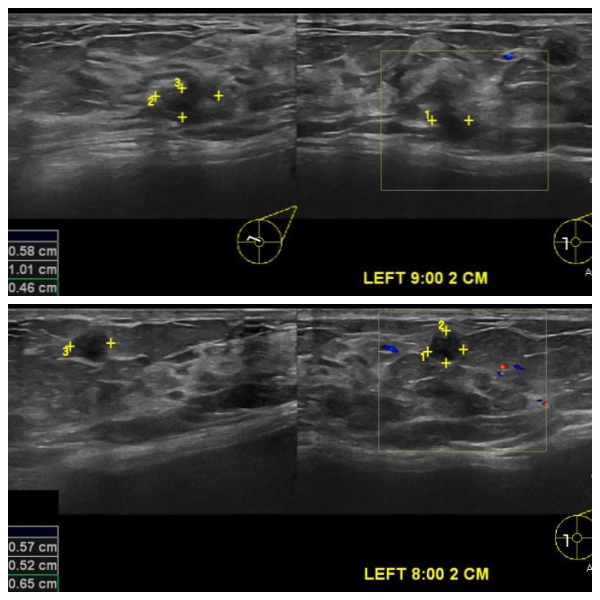

상기환자 좌측 유방의 통증과 멍울로 내원하신 40대 여성분으로 유방초음파 시행 후

좌측 9시 방향에서 2cm 떨어진 거리의 혹과 좌측 8시 방향에서 2cm 떨어진 거리의 멍울

각각 조직검사 시행하여 두 멍울 모두 침윤성 유관암으로 진단 되었습니다.